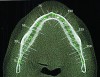

After initial consultation, the preoperative full-mouth radiographs were obtained from the referring periodontist (Figure 1). To address the immediate concern of the patient, replacement of the original crown on tooth No. 11 was provisionally secured to the supporting root. Diagnostic study casts were made of the existing clinical conditions (Figure 2). A complete dental and medical assessment and identification and explanation of treatment objectives was performed. The patient was referred back to the periodontist for confirmation of the implant and periodontal treatment proposals. This included a cone-beam computed tomography (CBCT) scan of the mandible (Figure 3) to aid in optimal implant placement.8 This was then coordinated with the development of the prosthetic sequencing and design. After presentation of the completed treatment plan to the patient, informed consent was obtained.

Fig 3. Pre-treatment CBCT, selected occlusal image

Figure 3